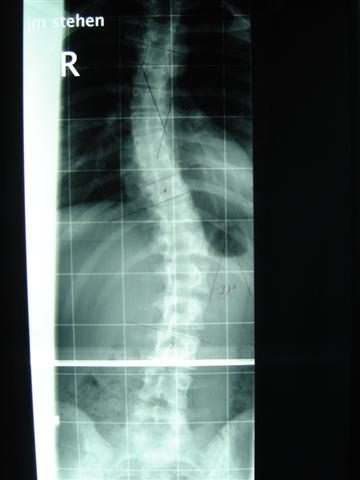

ich war heute in Dresden zum Röntgen gewesen. Musste erst zur Anmeldung, den Schein fürs Röntgen holen und dnan zum Röntgen gehen. Dort stand oben, das ich nur im Tgaeskorsett geröngt werden soll. Wir uns dann beschwert, weil aj nciht im Nachtkorsett geröngt wurde. Also ham se bei der Anmdelung vom dem Orthopädiehaus angerufen und ich konnte doch noch geröngt werden. Und als der Oberarzt die Röbis vermessen hat konnte er es fast selber nicht fassen!! Mein Tgaeskorsett korrigiert die lumbale Krümmung von 37° auf 12° !!!!! Ihr könnt euch gar nicht vorstellen, wie happy ich in dem Moment war, weil ich da die ganze Zeit an Fine und ihre Korsetts denken musste. Meine obere Krümmung wird im Tageskorsett nicht korrigiert, weil diese sehr weit oben sitzt und mein Arm einschläft, wenn er angehoben wird. Aber von den 34° ohne Korsett sind 28° es steht zwar 18° auf dem röbi, aber der Unterschied zu den 12° ist doch zu groß. Wir haben die Röbis auch fotografiert, ich stelle die Bilder dann demnächst hier rein. Im Nachtkorsett ist die untere Krümmung 13 °, und weil die irgendiwe im Liegen nicht die ganze WS röntgen können, kann die obere nicht vermessen werden

Noch mal die Werte im Überblick:

1. Röntgen, 1.3.05: 29° im BWS-Bereich, 32° in der LWS

2. Röntgen, 25.4.05: 34° in der BWS und 37° in der LWS (beides um 5 grad verschlechtert, die Ärzte hatten mir nicht mehr zu viel Hoffnungen gemacht)

3. Röntgen im Korsett, 29.8.05: 28° und 12°